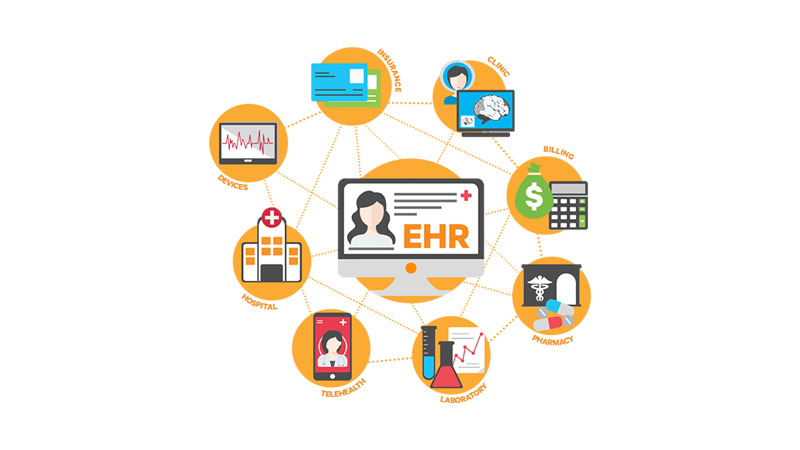

Wearables, apps and the “internet of medical things” are redefining the concept of patient care, as providers strive to deliver more personalized services with just a few taps. As patients become more empowered to make better choices when it comes to their health, the challenge is for the healthcare IT infrastructure to support these new technologies.

- Innovative wearable technologies and remote patient monitoring are enabling the growth of telemedicine. All of these technologies are generating large amounts of data that needs to be distributed securely and efficiently.

- Rethinking healthcare IT architecture and deploying small, branch data center locations supports a variety of healthcare functions including EMR systems, digital imaging and advanced telemedicine solutions to ensure fast, easy access to information.

- With a connected, intelligent IT infrastructure, healthcare organizations can simplify the management of healthcare IT and improve decision making for more efficient and reliable operations.

- Just as data collected from IoT-enabled devices is being used to improve patient outcomes, intelligent hardware, software, and services are enabling visibility and data-driven insight to improve performance and efficiency across your distributed IT and physical infrastructure.

- Connected devices and app-based technology puts key operating parameters at your fingertips improving communications and worker productivity.